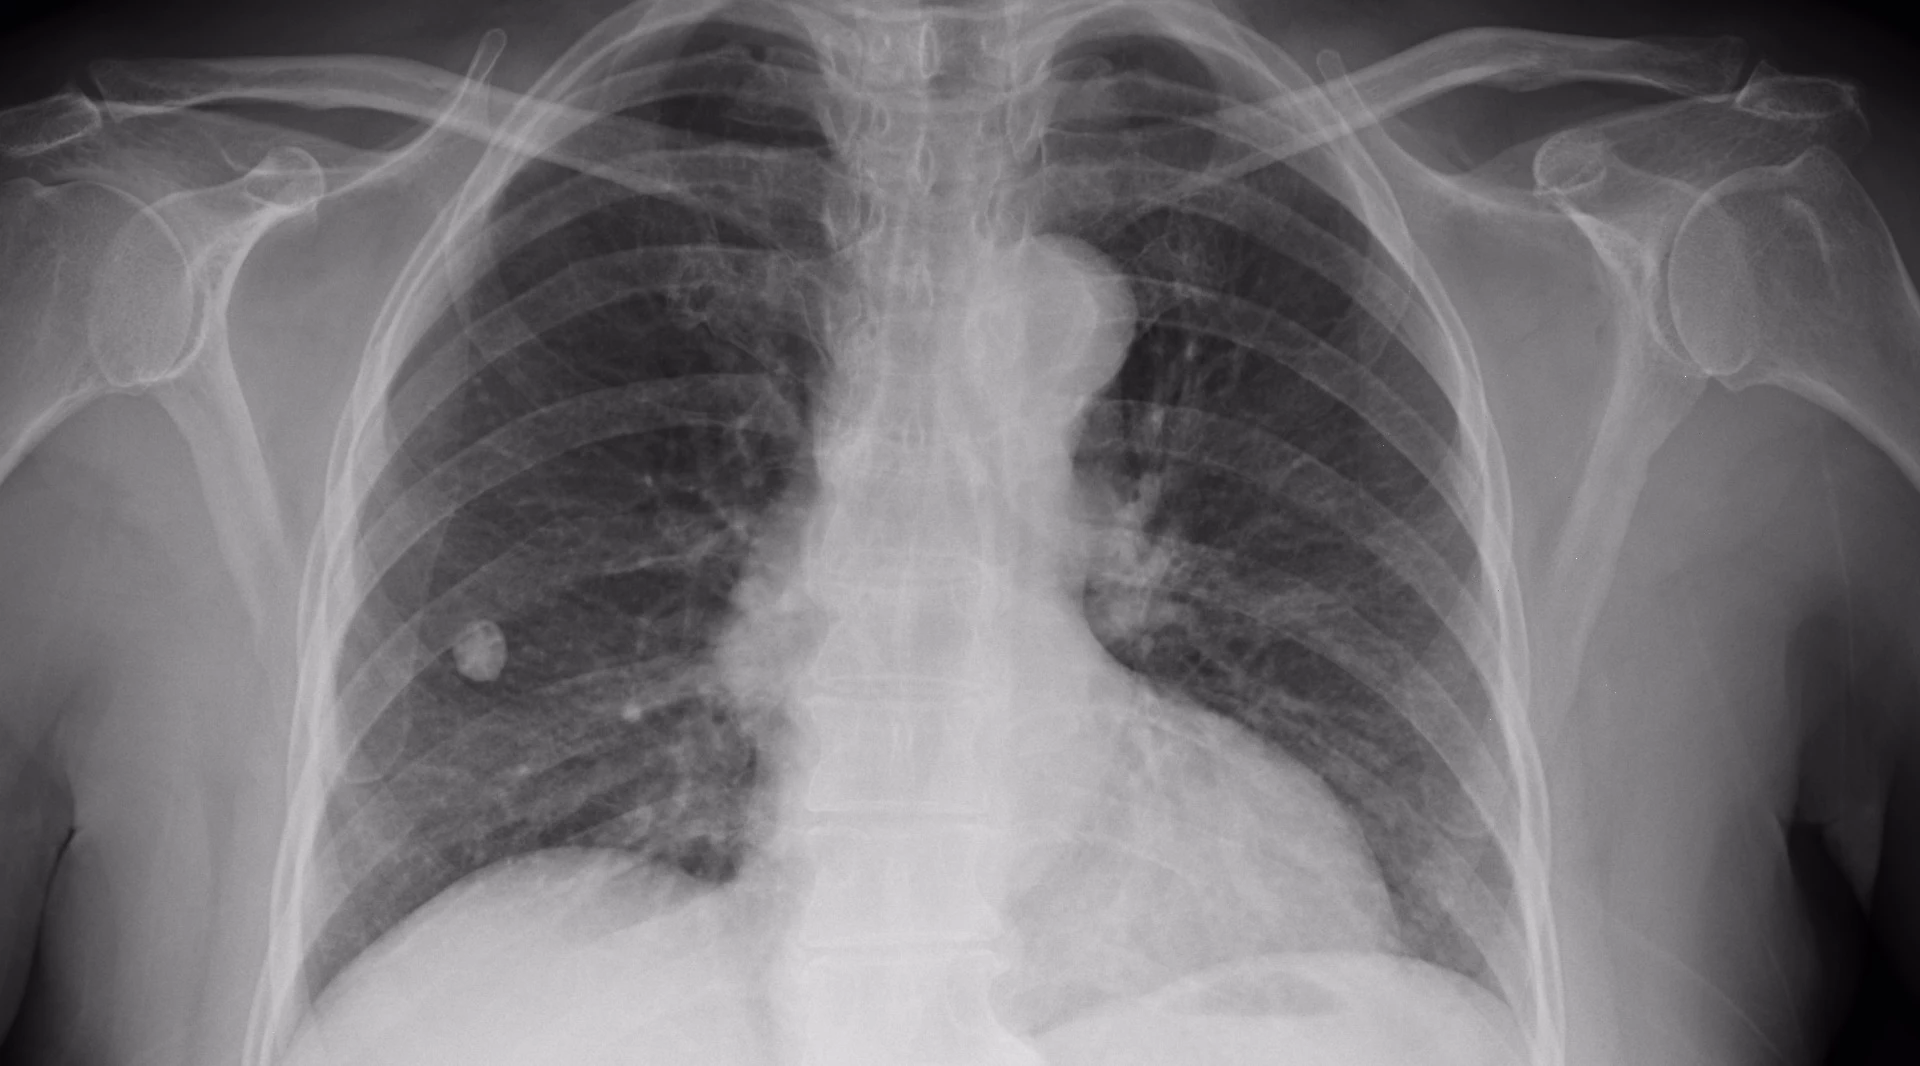

Infervision's AI Scholar software draws together over 50 deep learning algorithms in search of fast, accurate cancer diagnoisis

Predominantly used in early-stage lung cancer screening, the system started out with a huge stock of digital health records dating back to 2003 and employed technologies from GE Healthcare, Nvidia and Cisco, as well as more than 50 deep learning algorithms, to refine its diagnosis techniques into a tool it calls AI Scholar.

According to China's Toutiao news site, the Infervision system triples the speed at which radiologists can diagnose CT scans, and has helped reduce the rate of missed cancer diagnoses by some 50 percent.